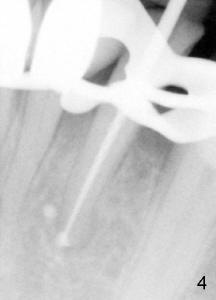

Sixty-two year old Chinese man presented to my office for new patient exam in June 2009. He has history of bruxism and wears night guard (Fig.1). The tooth #25 has incisal composite (*) with mild percussion. PAs show + PARL associated with #25 (Fig.2) and possible missing one canal (Fig.3; arrowheads point to possible 2nd root). RCT retreat was suggested. Extraction and implant were proposed as an alternative. In the next two 6-month appointments, he complained of mild pain in lower front tooth sometimes. RCT retreat was initiated on June 16, 2010. After removing composite, GP was removed with Chloroform and hand files. WL was determined by Root XZ at 15 mm. Debridement was done with hand files until #20 and rotary files until 30/.06 (Fig.4). The second canal was not found. It appears that some of GP was pushed outside of apical constriction (Fig.5 after Cavit). Twelve days later the patient returned to finish RCT retreat. It appears that symptoms improved after initiation of RCT retreat, although percussion is still mild. After removing Cavit and redebridement with #30 hand file, #10 precurved K file was inserted several times at different directions, hopefully getting into 2nd canal, which was not found. RCT filling was finished using AH Plus paste, master cone, lateral condensation with 1 medium fine accessory GP and vertical condensation (Fig.6). Composite build up was done immediately. Six months later, the patient insisted that pain is reduced substantially, but there is still mild percussion. PA shows persistent PARL (Fig.7 with outline with 2nd root (arrowheads)). Twelve months after RCT retreat, the patient is symptom-free, but objectively is not (including mild percussion and slightly enlarging PARL (Fig.8)). The 2nd canal is apparently lightly filled (red arrowhead).